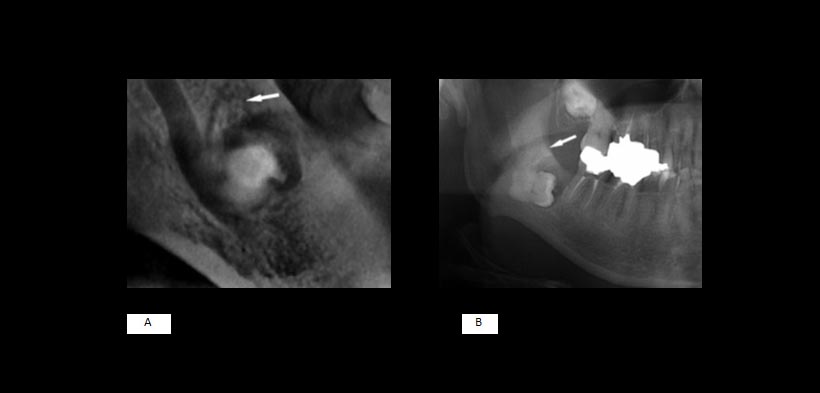

Fig1. (A y B) imágenes de la CTCB. Mandíbula izquierda (varón, 54 años). Las imágenes de la tomografía revelan claramente un canal estrecho superior procedente del foramen mandibular (Tipo I, flechas)